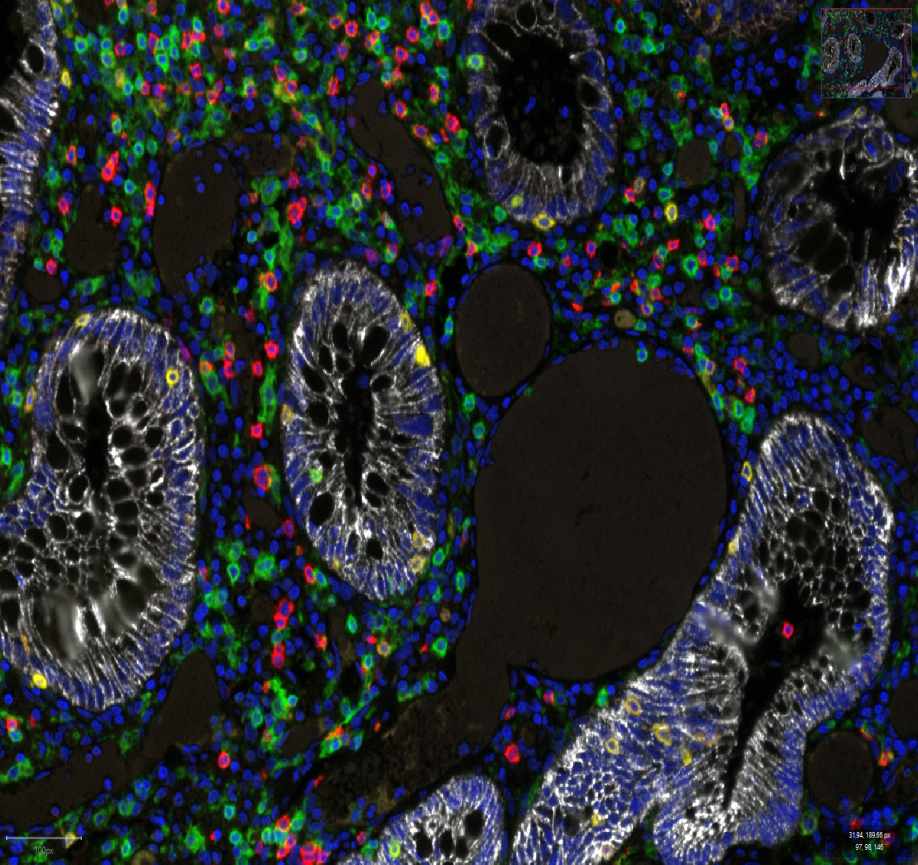

Vectra is a state-of-the-art tissue image analysis system.

The platform provides basic and advanced slide scanning and image analysis requirements – from single marker quantitation on whole sections of tissue microarrays (TMAs), to combined morphological and multiplex marker analysis of cells in tissues.

The software generates flow cytometry-like data and allows spatial analysis of tissue elements. Advanced tissue segmentation software allows the system to be trained to recognise features of interest based on morphology and/or marker staining.